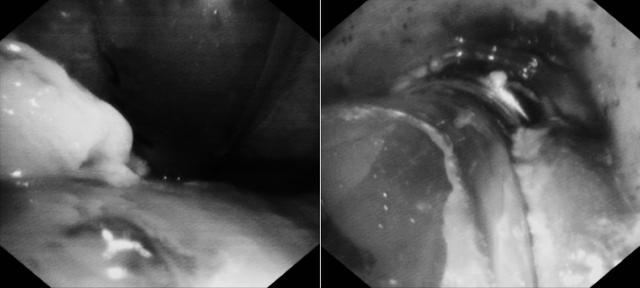

整个操作必须极度轻柔、精准,既要彻底清除梗阻,又要最大限度避免对脆弱气道黏膜的医源性损伤,并严防异物脱落导致二次梗阻。

(▲清理的部分食物残渣铺满纱布)

历时整整一小时的持续“毫米级”作业,团队凭借默契的配合与精湛的技术,终于将气道内的堵塞物成功清除。随着气道恢复通畅,患者氧合指标迅速改善,最危急的关卡被成功突破。